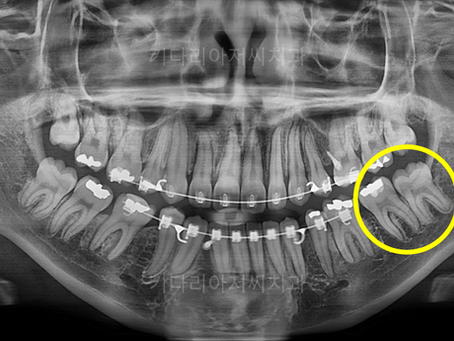

연산역치과 키다리아저씨치과에서 시행한 교정 중 충치치료를 병행한 치료사례